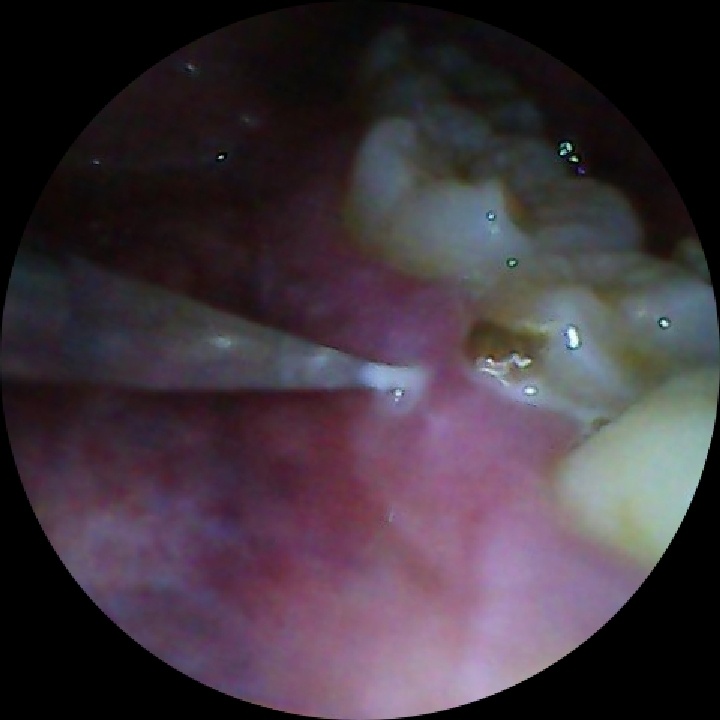

之后检查又发现一个灯下黑。怀疑也是。顺着咀嚼面打了一个洞,发现里面确实是一个龋齿,而且坏的挺大。然后就是惨不忍睹的磨,我就感觉跟往我骨头里面钻骨髓一会的疼医生问我打麻药不。我说不用。没好意思问要不要钱,肯定是要钱的我就硬挺过来了。

磨的整个牙都快空了,然后补上最便宜的材料。一共花了200块钱。还送了牙刷牙膏牙线湿巾等等。